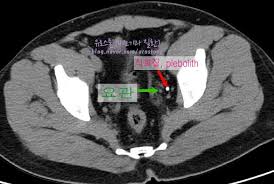

3. CT

- CT는 초음파보다 정확하게 돌의 위치를 찾아줍니다 .다만 CT역시 엑스레이를 여러장 찍는것과 다를 바 없으므로 1년에 한두번 정도만 찍도록 관리가 필요합니다.